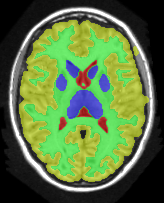

![]() |

|

No min-margins |

| a-exp [7, 8] | QPBO [25, 8] | ours |

Figure 16 shows the results for Subject 1 with (and without) min-margins and Hedgehog prior. The third row shows the results when not using min-margins. Path-Moves converged after two iterations to a lower energy than a-exp, which converged after six iterations. In this case a-exp local minimum was due to the Hedgehog prior, see last row.

Table 1 compares the precision, recall and F1 score for each region individually, where . The higher F1 values correspond to better segmentation. In general, QPBO was unpredictable as in some cases it found the optimal solution and in other cases it left a large number of pixels unlabeled.

Table 2 show the results after dropping the hedgehog prior. In terms of Path-Moves, the mainly affected label after dropping the Hedgehog prior is the sub-cortical gray matter, as it started to grab parts of the gray matter, see Fig.16 second row, last column. Comparing Tables 1 and 2 it is clear that QPBO and a-exp benefited the most by introducing the hedgehog prior.